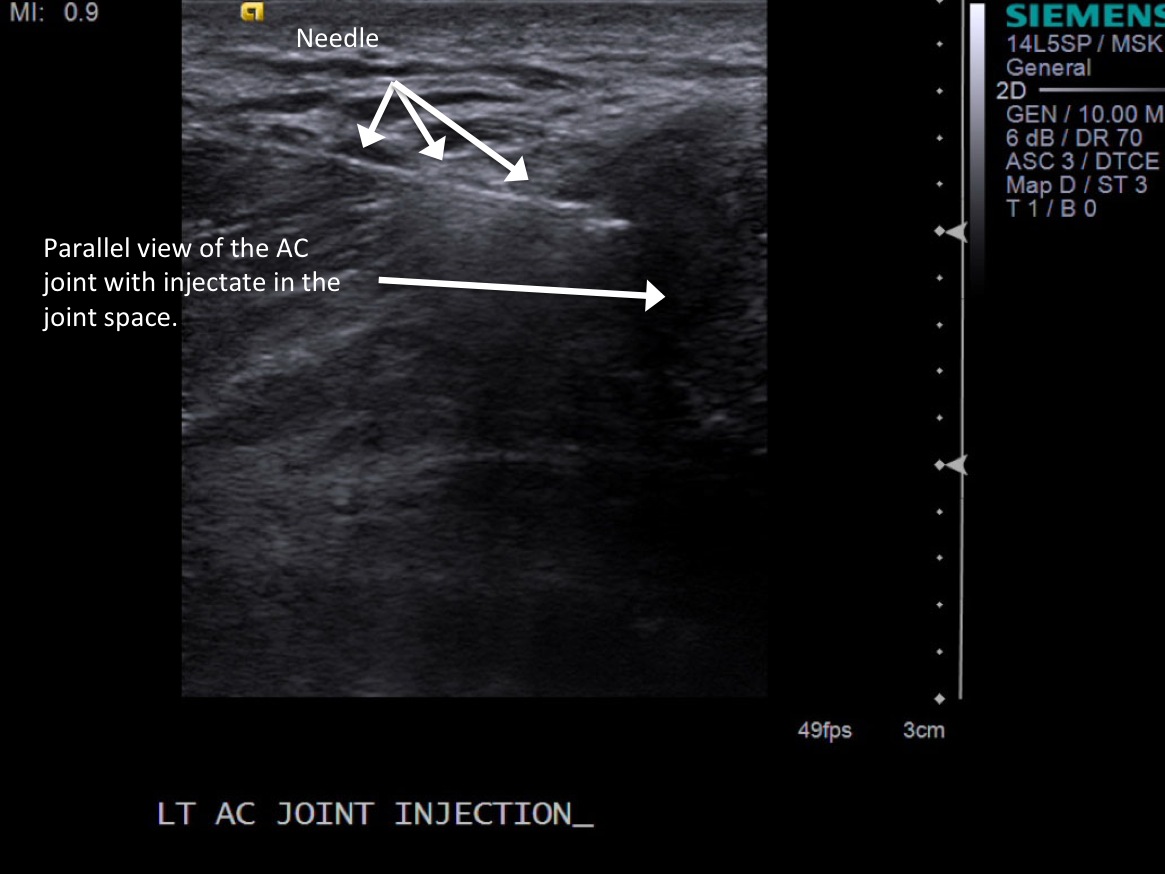

7. Under ultrasound guidance, advance needle into the AC joint. Test inject with 1% lidocaine. If no resistance, switch 1% lidocaine for injectable steroid mixture. If there is resistance, reposition needle and test inject again. Inject 0.5 -1 cc of injectable steroid/anesthetic mixture.

• descriptiondescription

8. Pull needle out and follow standard post-procedure protocol with cleaning off the skin and placing a bandage. Post procedure transverse images demonstrating distention of the joint with steroid and anesthetic.